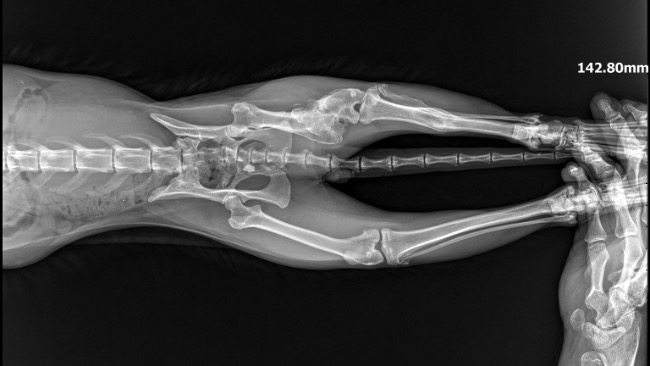

Na pewno większość z was zna historię tej dwójki. Od wielu tygodni zgłoszenia do różnych organizacji, nikt nie pomógł. Dostaliśmy to zgłoszenie 26.08- dwa zaniedbane, koty przy bardzo ruchliwej ulicy Mazowieckiej- żyły w bramie dokarmiane przez mieszkańców. Jeden kotek w złym stanie. Niezwłocznie udaliśmy się na miejsce. Akcja okazała się trudniejsza niż myśleliśmy… wysoka zamknięta brama, ciężka do przejścia, oraz bardzo nieufne koty, uciekające od klatek. Jedną kotkę udało się złapać po kilku dniach. Trafiła do lecznicy, wykonaliśmy diagnostykę, przeszła zabieg stomatologiczny usunięcia połamanych zębów. Z kotkiem w złym stanie było ciężko, omijał wszystko. Udało się go złapać dopiero 30.09 po wielu godzinach łapanki. To kastrowany kocurek. Niestety faktycznie jego stan jest bardzo zły. Wykonaliśmy szereg badań- Rtg stare złamanie kości udowej, USG- powiększone, zatarte nerki, badanie krwi niestety potwierdziło przewlekłą niewydolność nerek. Wyniki są bardzo złe, a rokowania ostrożne. Na nieszczęście ma też połamane zęby, które pogarszają sprawę, te w najgorszym stanie zostały usunięte. Jeśli uda się poprawić parametry nerkowe, przejdzie pełny zabieg stomatologiczny. Ma też świerzbowca usznego, oraz wielki kamień woszczynowy w uchu, zatykający praktycznie kanał słuchowy (który został usunięty) Jest źle… Ale walczymy, łatwo się nie poddamy. Szkoda tylko że szybciej do nas nie trafił, pewnie rokowania byłyby lepsze. Nasza sytuacja finansowa jest fatalna. Mamy kilkanaście tysięcy długu w różnych lecznicach. Musieliśmy wstrzymać przyjmowanie kolejnych kotów (a rzadko odmawiamy pomocy) Mamy pod opieką około 40 kotów, wiele z nich chore, wymagające zabiegów i diagnostyki. Jeśli nie uda nam się zebrać pieniędzy i załatać dziur, nie będziemy mogli dalej pomagać. Chore zwierzaki nie mogą czekać na „lepsze czasy”- pomożecie ?